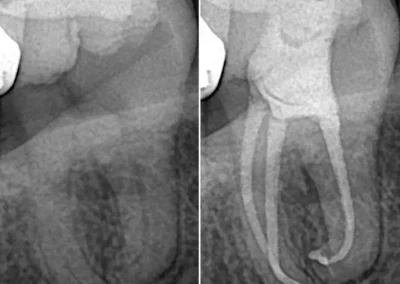

Periapical X-rays

If sharp pain or swelling appears near a specific tooth, a periapical scan helps identify decay, infection, or bone loss. It captures the full tooth from crown to root, offering a complete picture of its condition. Our advanced digital sensors deliver crisp results in seconds while keeping exposure low.